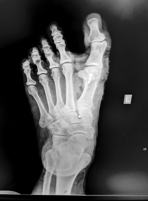

Ο ακτινολογικός έλεγχος είναι απαραίτητος ώστε να εκτιμηθεί η βαρύτητα της βλάβης, μέσω μέτρησης των γωνιών μεταξύ των μεταταρσίων, αλλά και για τον σχεδιασμό της ενδεχόμενης επέμβασης.

Έχοντας στη διάθεσή μας πολλαπλές τεχνικές, ο κλινικός και ακτινολογικός έλεγχος καθώς και απαιτήσεις της καθημερινότητας του ασθενούς καθορίζουν την καταλληλότερη επέμβαση.

Εικόνα: αποκατάσταση βλαισού μεγάλου δακτύλου με οστεοτομία τύπου chevron